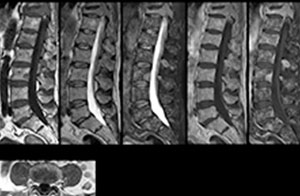

cervical spine mri in ed

Cervical spine routine exam

This patient presented with headache that was worse with neck flexion and we see a Chiari 1 malformation with low-lying cerebellar tonsils as well as some degenerative cervical thrombolytic change.